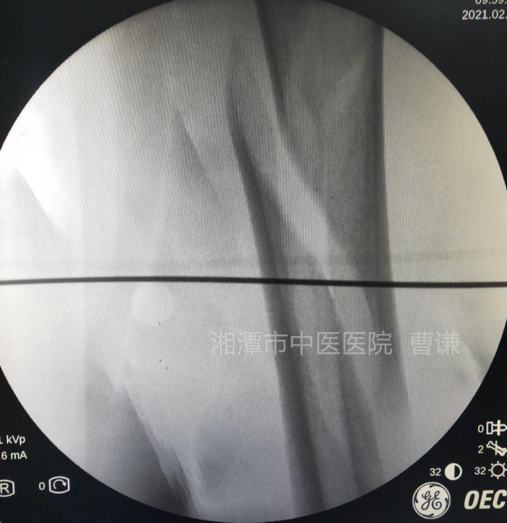

麻醉生效后,常规消毒铺无菌巾,先在体表放置一根克氏针透视,确定骨折端适宜钢丝捆扎的部位。

在透视确定的平面上,分别在大腿前方及稍偏后的外侧做约1.5cm小切口,用一把中号弯钳夹持丝线

(建议采用5号肌腱线或最粗可吸收线,不容易断,注意夹线时多折几折,这样另一把止血钳很容易夹住)。

自后外侧切口插入,触碰到骨干后向下滑走,沿骨干后方贴骨膜外伸至断端内侧。